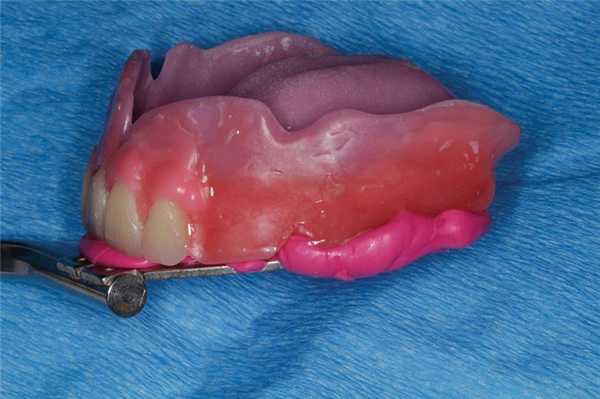

Отправной точкой для изготовления полного съемного протеза является определение вертикального и горизонтального положения передних зубов верхней челюсти. Это достигается за счет использования пластинки базисного воска и воскового валика (фото 1).

Фото 1. Восковый валик верхней челюсти с маркировкой срединной линии и высокой линии улыбки.

Чтобы проверить правильность положения, можно зафиксировать их в восковом базисе (фото 2). Для подтверждения правильности положения зубов врач должен проверить произношение пациентом звуков «Ф» и «В»: при этом пациент должен касаться передними верхними зубами линии перехода влажной части нижней губы в сухую. Для регистрации данного положения врач может попросить пациента сосчитать до 50 или 60 в голос. С диагностической целью врач также может получить фотографии положения воскового базиса и зубов в состоянии покоя, при высокой улыбке, а также - в профиль. Дополнительно можно записать несколько видео пациента в ходе разговора, после чего все эти данные можно передать зубному технику.

Фото 2. Вид воскового валика с установленными зубами 8 и 9.